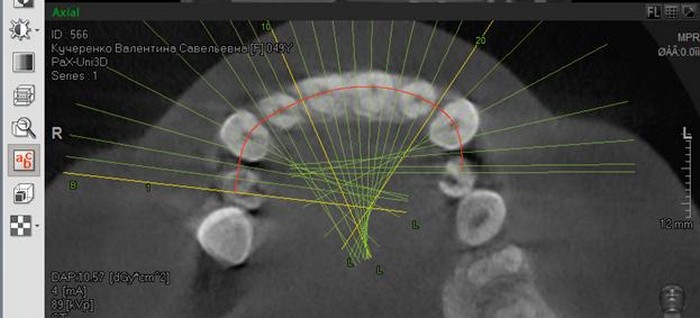

О самом кабинете рассказал его владелец, Александр Пономаренко:

- Мы арендуем это помещение и установили свое оборудование. Такого нет нигде в области из-за чего и была договоренность, чтобы поставить его в самой большой больнице. Привезли этот южнокорейских компьютерный томограф, который как для детей безвредный, так и для взрослых людей. Беременных снимаем, потому что у нас минимальная доза облучения. Работаем на таких же условиях как и все. Никто же велосипед не придумывал. Тем более, что мы и деньги пошли заплатили в банк и банковский чек им принесли.

- Мы очень часто посылаем людей сделать снимок именно там. Имея 3D-изображение мы можем на компьютере со всех сторон посмотреть зуб, корень, понять строение кости, заглянуть туда, куда обычным рентген аппаратом мы в принципе не сможем посмотреть. Если сравнивать его с обычным рентгеном, то обычный нам дает где-то 10% необходимой информации, в то время как 3D-изображение сделанное этим аппаратом — 100%.